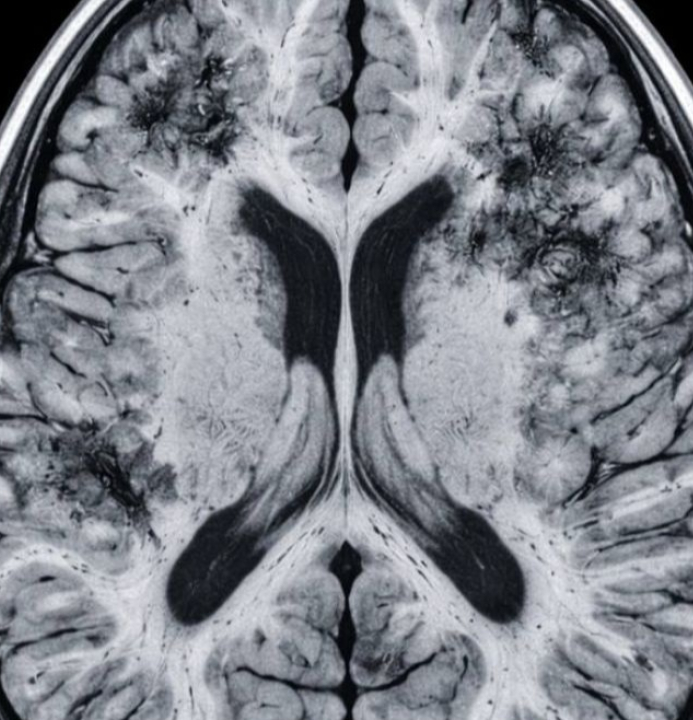

SAÚDE | Mais de 55 milhões de pessoas no mundo vivem com algum tipo de demência, segundo estimativas da Organização Mundial da Saúde (OMS). Uma pesquisa conduzida na Universidade de Harvard pelo neurologista Rudolph E. Tanzi, codiretor do Centro Henry e Allison McCance para Saúde Cerebral do Hospital Geral de Massachusetts, investiga genes ligados à doença de Alzheimer e criou estratégias para manter o cérebro ativo e saudável.